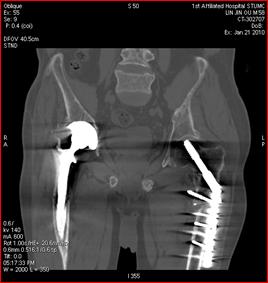

高能量X射線可以去除高密度金屬引起的偽影

常規(guī)CT 寶石能譜CT

140keV能量成像可以除去金屬引起的偽影,更加清晰觀察術(shù)后情況